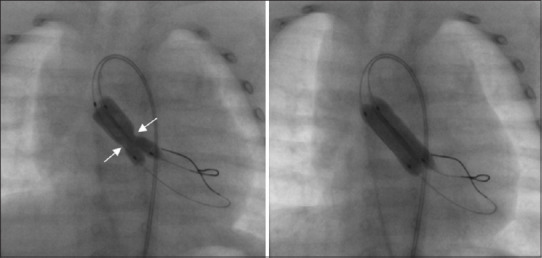

We hypothesized that a double-balloon technique would be associated with a lower likelihood of aortic regurgitation (AR) following balloon aortic valvotomy (BAV). We present the short- and mid-term outcomes of the double-balloon technique for BAV. Fifty consecutive patients (median age: 6.5 years; interquartile range (IQR): 3.8-13.2) underwent BAV using double balloons. Prior AR was present in 17 (34%). Following BAV, the peak-to-peak gradient reduced from 80 (66.5-100) mm Hg to 24 (16-35) mm Hg (P < 0.0001); 10 (20%) had trivial AR, 18 (36%) had mild AR, 10 (20%) had moderate AR and none had severe AR. Four (8%) had transient arterial occlusion requiring anticoagulation. There was no procedure-related mortality or requirement for emergency open-heart surgery. The double-balloon technique offers a safe and effective alternative option for BAV in patients beyond infancy with relatively large annulus sizes. There is a low likelihood of postprocedural severe AR and the need for repeat procedures. Further long-term follow-up of this cohort is needed to ascertain long-term outcomes.